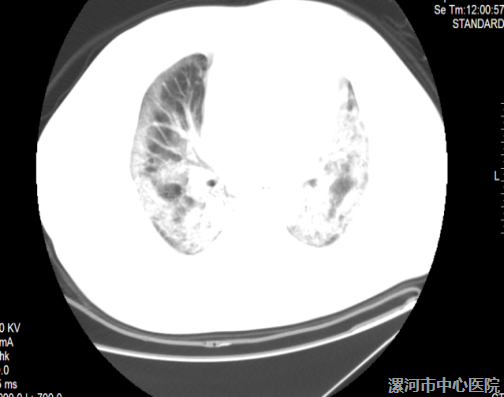

(图1.2为患者入院时肺部CT 2019-01-26)

患者于6日前饮酒后出现发热,最高体温39℃,伴咳嗽、咳黄痰,痰液不易咳出,伴腹泻、稀水样便。患者在当地诊所治疗效果差,遂来我院治疗。门诊以“发热待查”收入全科医学科,给予氧疗效果不佳,遂请我科柳彦涛副主任医师会诊。因患者呼吸急促、口唇发绀、呼吸困难,血氧饱和度难以维持,需急行机械辅助通气,遂转入我科进行抢救性治疗。